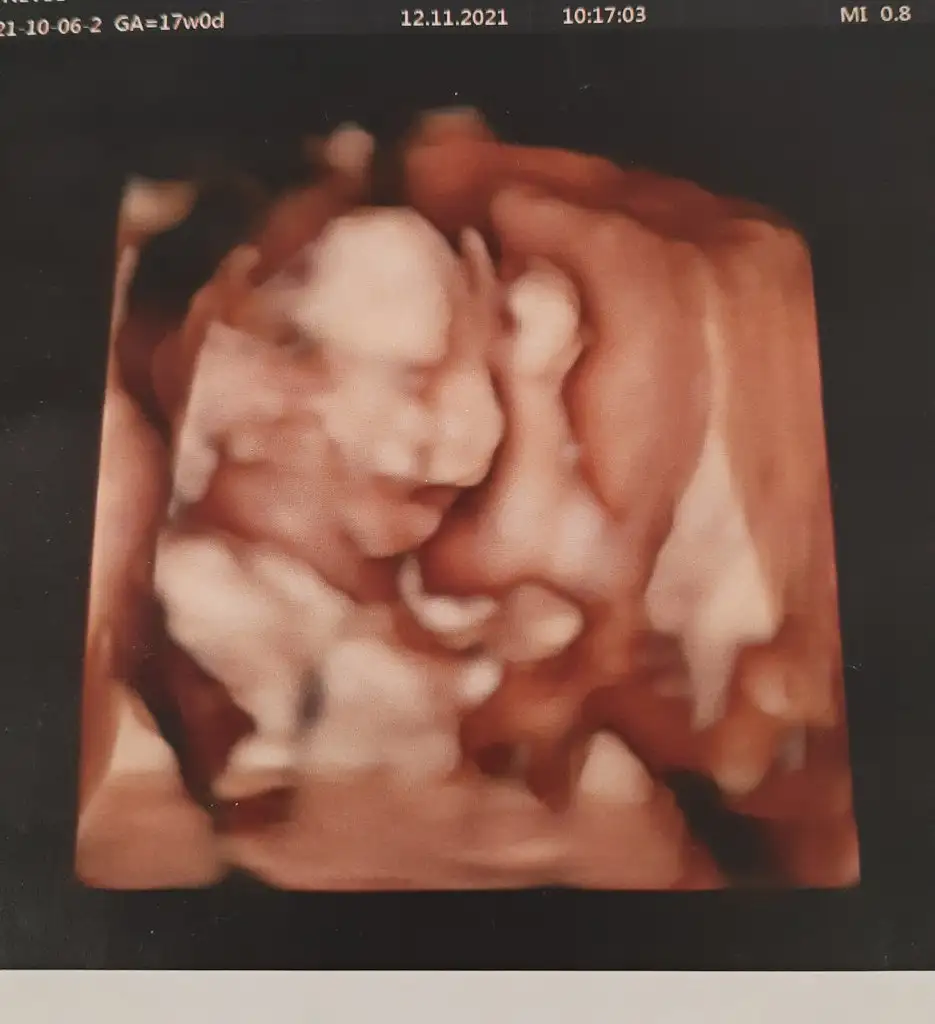

O zaman bir karşılaştırma da benden gelsin 😂 bu da benim bebenin döllenmeden sonra 5. Günkü hali 😂😂 sat a göre 20 günlük falan oluyor 😅 asıl değişim burda 😂

Resmen icimizde bi mucive tasiyoruz canim, anne olmak gercekten cooooook farkli 🥰🥰